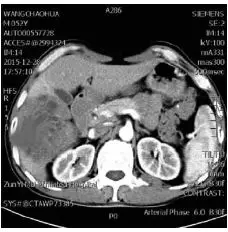

磁共振上腹部快速自动化增强扫描流程的初步研究 罕见病 疑难病 会诊平台 专家会诊 网上会诊 医学影像

磁共振上腹部快速自动化增强扫描流程的初步研究 罕见病 疑难病 会诊平台 专家会诊 网上会诊 医学影像

磁共振上腹部快速自动化增强扫描流程的初步研究 罕见病 疑难病 会诊平台 专家会诊 网上会诊 医学影像

长海医院经验分享 5分半钟完成高质量的腹部mri检查 磁共振爱好者 微信公众号文章阅读 Wemp